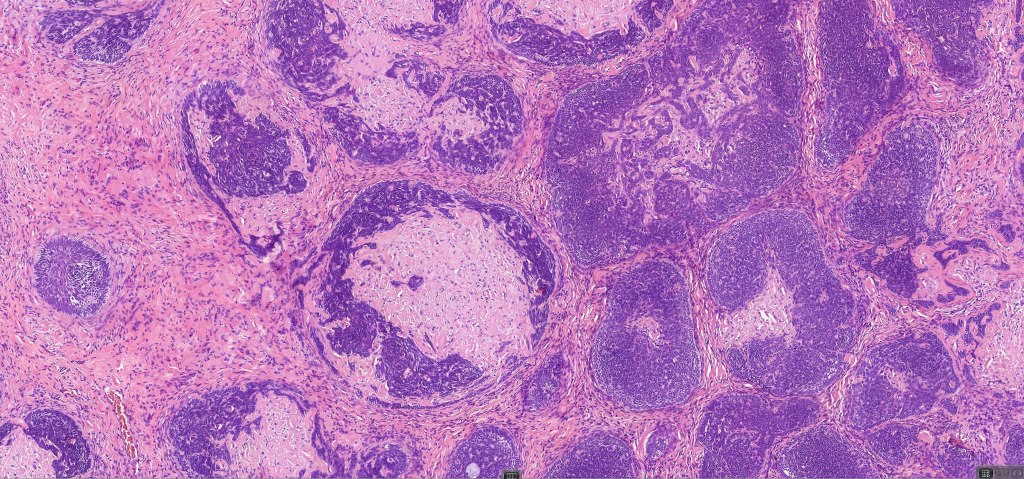

•A rich fibromyxoid mesenchymal stroma with variable papillary mesenchymal bodies (sometimes these are absent)

•Trichogerminoma is a distinctive variant being composed of tumor nodules with basaloid cells surrounding pale or eosinophilic micronodules (Zellballen)

Trichoblastoma can be distinguished from BCC by the absence of retraction artifact and stromal mucin deposition. BCC does not show papillary mesenchymal bodies. Immunohistochemical differences are shown in the table below.